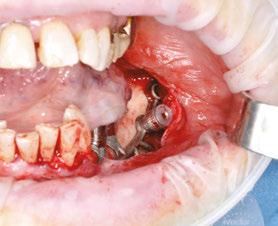

The procedure begins with local anesthesia at multiple points, vestibular and lingual, from the symphyseal region to the ascending ramus. However, an infiltration in the lingula of the mandible is not necessary. The incision is performed using the technique described above (Figures 5A and 5B).

It is imperative to carefully reflect a full-thickness flap following the periosteum. After reflection, an atraumatic periosteal expansion using a soft brush (Figure 6) will allow for the flaps to be repositioned without tension over the implant and bony surfaces at the end of the procedure.

Figures 8A-8D: Placing the subperiosteal implant and monitoring its adaptation Figures 5A and 5B: 5A. Initial clinical view. 5B. Access flap Figure 6: Periosteal expansion using a soft brush Figure 7: Prehension of the subperiosteal implant

After the soft tissue is prepared, the bony surface is carefully cleaned. For easy insertion, the healing abutments are left in place, and the implant is held firmly with hemostatic forceps (Figure 7). The implant is inserted via distal translation in the direction of the angle of the mandible, then a mesio-anterior rotation. The surgeon must control the lack of mobility and the adaptation of the implant to the bony surface at all points (Figures 8A, 8B, 8C, and 8D).

To ensure the implant is stable during the osseointegration period, an osteosynthesis screw is placed in the prepared space (Figures 9A, 9B, 9C, and 9D).